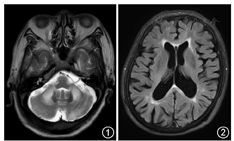

患者男性,67岁,农民,因"双下肢不自主抖动8年,加重伴走路不稳1年半"于2018年2月6日入院。患者8年前出现双下肢不自主抖动,仅在站立时出现,坐位或平躺时消失,症状较轻,不影响日常生活。1年半前患者感双下肢抖动较前加重,伴走路不稳、东倒西歪,不能走直线,上下楼梯需扶物,症状逐渐加重;8个月前出现双上肢不自主抖动,表现为拿筷、端碗时明显晃动。于当地医院诊断为"帕金森病",服用多巴丝肼片0.125 g,每日3次,均在餐前1小时服用。服药2个月左右,患者肢体抖动及走路不稳症状改善不明显,为明确诊断转来我院。患者自发病以来,无发热,无精神行为异常,无记忆力减退,无头晕,无视物障碍,无吞咽困难,无肢体麻木,无意识障碍,饮食睡眠正常,无快速眼球运动睡眠期行为障碍现象,近2年尿频、尿急,夜尿4~5次,大便正常,体重未见明显变化。家族史:患者父亲75岁时因胆道系统疾病去世,母亲70岁去世,具体原因不详,生前均无类似表现;患者有姐姐及妹妹各1人,均无患者类似表现。患者育有2女,大女儿及其子体健;二女儿体健,其子被诊断为"自闭症、多动症"。入院时体检:意识清楚,语言流利,正确对答,眼球各方向活动自如,无眼震及复视,双侧鼻唇沟对称,伸舌居中,四肢肌力均Ⅴ级,肌张力正常,深浅感觉检查未见明显异常,双侧轮替运动灵活,双侧指鼻试验、跟膝胫试验欠稳准,指鼻时可见意向性震颤,左上肢静止性震颤,双下肢直立性震颤,闭目难立征阳性,宽基底步态,四肢腱反射(++),双侧病理征未引出,脑膜刺激征阴性。辅助检查:血常规、肝肾功能、电解质、同型半胱氨酸、血脂分析、肝炎系列、梅毒、HIV化验未见明显异常。腰椎穿刺颅内压110 mmH2O(1 mmH2O=0.009 8 kPa),脑脊液无色透明,白细胞计数为0,脑脊液蛋白0.66 g/L(正常值0~0.45 g/L),葡萄糖及氯化物正常,细菌涂片(-)。肌电图神经传导及针极肌电图均未见明显异常。MMSE:28分(小学文化)。卧立位血压:站立1、3、5 min时与卧位时相比收缩压差值均<20 mmHg(1 mmHg=0.133 kPa),舒张压差值均<10 mmHg。泌尿系超声:前列腺结石,残余尿<10 ml。颅脑MRI:双侧桥臂、双侧大脑半球白质对称分布的异常信号(图1,图2)。脆性X染色体基因检测:通过PCR扩增结合微流控毛细管电泳技术,本患者FMR1基因5′UTR区的CGG重复次数为101次(正常或临界重复次数<45次,图3,图4),重复次数在前突变范围内。诊断:"脆性X相关震颤/共济失调综合征"。给予氯硝西泮0.5 mg,每日1次治疗,1周后加量至0.5 mg,每日2次。治疗1个月后,临床症状改善不明显。

FXTAS多在55岁以后发病,男性多见,病程逐渐进展,以意向性震颤、小脑性共济失调步态、帕金森症候群、认知功能减退、周围神经病及自主神经功能障碍为主要临床表现。通常意向性震颤最早出现且进展缓慢,可见于80%的患者,以手部震颤最明显,头部震颤也较常见。50%的患者可见小脑性共济失调步态,表现为站立不稳、步基增宽,一般晚于震颤出现;国外报道,患者多在病程9年左右时需依靠助行器行走,病程16年左右不能下床[6]。帕金森症候群见于30%的患者,临床症状较帕金森病轻,行动迟缓、身体僵硬更常见[2]。周围神经病变特点为长度依赖、感觉运动神经均受累、轴索损害为著。自主神经功能障碍表现为直立性低血压、性功能减退及尿频等。认知功能损害主要表现为执行功能减退。除此之外,还可能合并焦虑、抑郁、睡眠障碍、头痛、甲状腺功能异常、不宁腿综合征等症状[7]。颅脑MRI双侧小脑中脚对称性T2高信号为本病特征性的影像表现,可见于60%的男性患者及13%的女性患者[6]。皮质下白质病变也较常见,部分患者FLAIR序列可见胼胝体压部高信号[8]。治疗方面目前尚无特效药物可延缓或阻止此病的进展,临床上仅能对症治疗,如氯硝西泮、扑痫酮、阿罗洛尔等可减轻震颤,左旋多巴可改善帕金森样症状,平衡康复训练对步态不稳有效。另外,脑深部刺激也可减轻震颤,但可能加重共济失调症状[2,9]。

本例患者59岁起病,慢性进展病程,临床上有意向性震颤、小脑性共济失调及静止性震颤等表现,且颅脑MRI有小脑中脚对称性T2高信号征,临床及影像学均符合FXTAS诊断,进一步基因检测证实FMR1基因处于前突变范围,FXTAS诊断明确。因患者母亲已故,不能通过病史或基因检测进一步验证患者基因突变是否来源于其母亲;患者外孙"自闭症"亦提示脆性X综合征可能,但因多种原因未行基因检查。本患者以直立性震颤起病,且合并多种形式的震颤,进展缓慢,疾病早期很难根据震颤情况诊断本病,临床上需要与帕金森病、原发性直立性震颤、特发性震颤、多系统萎缩、进行性核上性麻痹等疾病鉴别。意向性震颤和小脑性共济失调为本病突出的临床表现,当同时存在时,应高度怀疑本病。